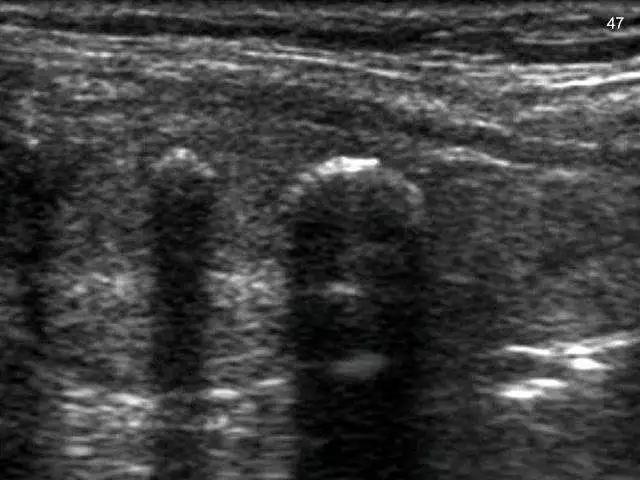

超声检查中钙化结节的直径>2mm,超声表现为强光团、片状、弧形或其他不规则形态的钙化灶。病理组织切片中观察形态不规则。

钙化结节的直径≤2 mm,超声表现多呈针尖样、颗粒样、点状、砂粒样。病理组织切片中观察圆形或砂粒体样直径60~100um。超声检查中≤2mm的钙化点反映的就是病理组织切片中观察到的微钙化,但超声检查的微小钙化发现率相对较低。